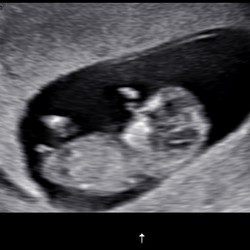

Ik begin het wat zwaarder te ervaren. Veel last van pijn in onderrug en heupen tijdens de nachten.. dus weinig slaap. Daardoor overdag minder energie. Verder ben ik heel blij dat ik de 32 weken heb gehaald. Ik heb namelijk vanaf 18 weken t/m 24 weken last van bloedverlies gehad. Dit lag aan dat mijn placenta te laag lag bij de baarmoedermond. Dit waren nogal stressvolle weken en zit sinds begin December dus ook al thuis in de ziektewet. Het liep dus anders dan ik had verwacht. Voor nu groeit ons meisje lekker en kijken we er naar uit om haar te ontmoeten! #uitgerekendop8Mei

32+2 van me 2de kindje. Heel veel last van me rug. En veel krampen in me onderbuik ( wat voelt als ongesteldheidskrampen). Ik doe teveel wat ik eigelijk niet aankan. En nog een dreumes van 1.5 die ook alle aandacht nog wil van mama. Van mij kan het niet snel genoeg gaan, ik ben er goed klaar mee.. baby loopt wel voor op de groei en ik heb teveel vruchtwater zal ook niet allemaal mee helpen..

Ik ben bijna 32 weken en het lijkt goed te gaan met een bewegelijke baby in de buik. De komende weken werk ik nog 32u pw tot half april. Dan even niets tot hij of zij er is, omdat we nu midden in de verkoop van mijn woning zitten kijk ik daar erg naar huis. Babyspullen staan bijv nog niet en we hebben ook nog niet alles gekocht omdat alles direct in de weg staat.. Ondertussen zijn we druk bezig met alles voor het nieuwe huis.